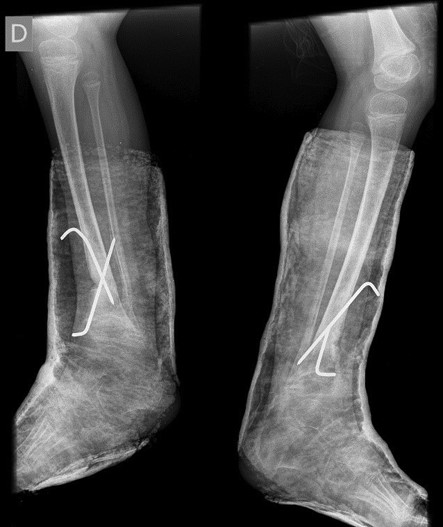

The X-ray showed a bowing of distal tibia, bilaterally, producing a varus deformity of 53 degrees (Fig. 2).

Surgical correction was scheduled. It was performed an opening wedge tibia osteotomy and filled the remaining gap with structural fibular graft. It was fixed with two crossed K-wires and cast immobilization. Both surgeries were performed at the same operative time (Figs 3 and 4).